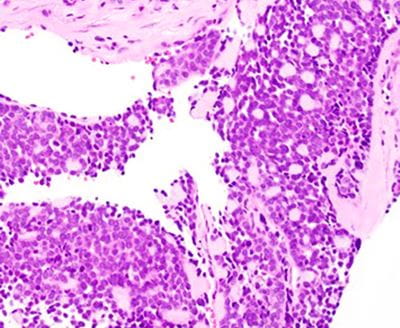

Microscopic findings

The tumor predominantly grows in the submucosal areas, forming cribriform nests, ductal structures, trabecular arrangements, or solid sheets. The tumor cells are basaloid with scant cytoplasm. Focal areas of squamous differentiation, characterized by eosinophilic cytoplasm, are observed. The overlying squamous mucosa exhibits high-grade dysplasia.